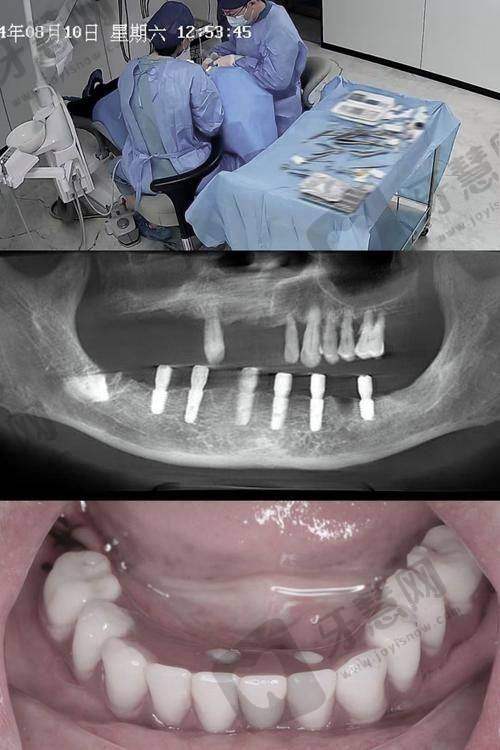

专精背景与经验:朱宋金医生是北京优贝口腔的主治医师,拥有20年牙科诊疗经验,还是口腔种植学硕士。他在口腔领域专精知识丰富,尤其擅长种植外科、复杂种植、即刻种植、种植美学修复及微创种植等项目。

临床成果:在临床实践中,朱医生成功完成了千例种植牙病例,展现出杰出的技术与专精能力。特别是在即刻种植牙和半全口种植牙技术方面表现出色。患者们对北京优贝口腔的种植牙技术和服务给予高度评价,这也从侧面反映出朱宋金医生的专精水平和诊疗成效值得信赖。